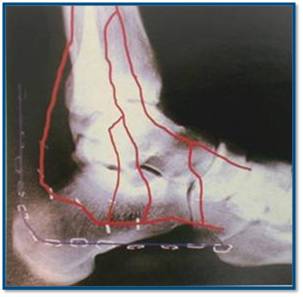

4. Решили оперировать? Это отдельная тема, нюансов и деталей полно. Если позволите, только два момента, которые здесь уже обсуждались. Доступ - именно L - образный, не надо стремиться перенести собственно разрез выше к подтаранному суставу. Это чревато некрозом лоскута. В приложенном файле - анатомическая реконструкция, объясняющая причину.